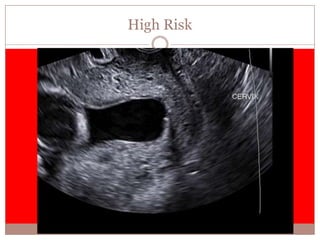

High Risk

 High risk of preterm birth

 Regardless of the fFN result

 Active management recommended

 Prevention of morbidity associated with

preterm birth.